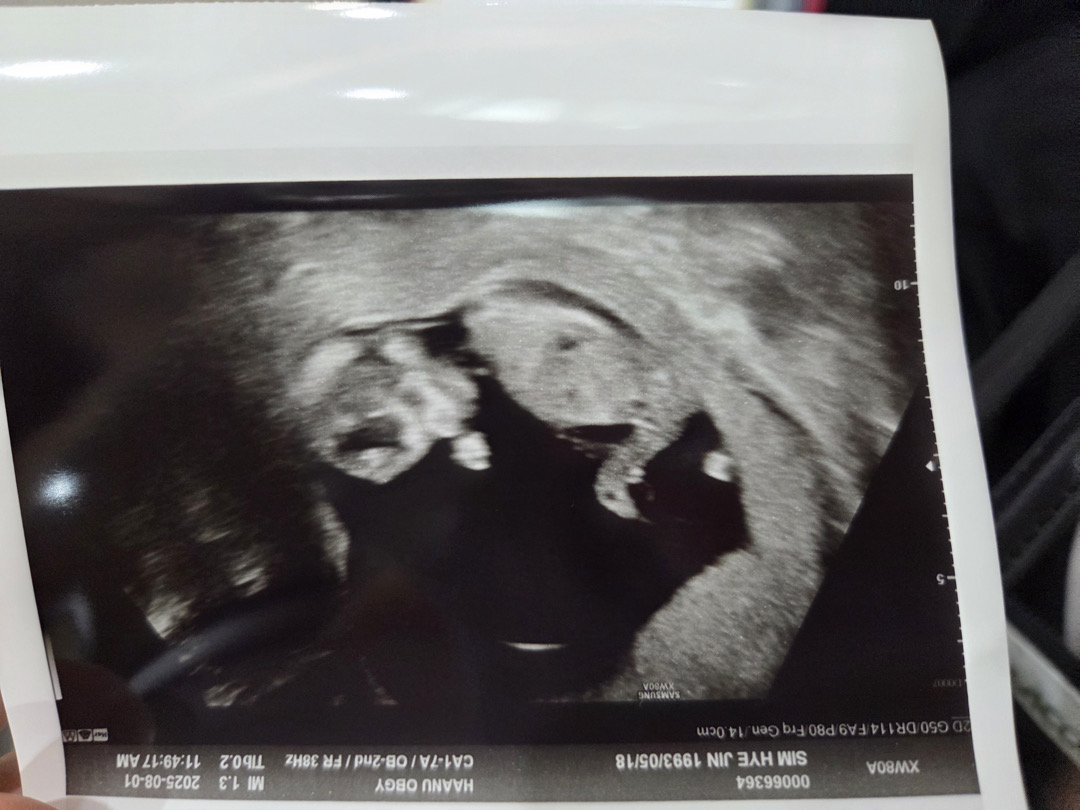

각도법이요 !!

12주차인데 어떰거같나용 아들같나요??